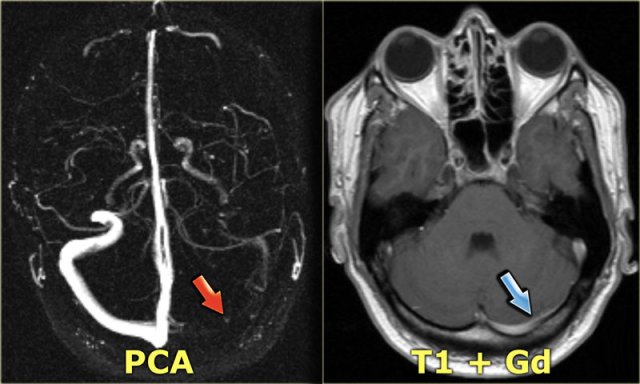

MR-venography

The MR-techniques that are used for the diagnosis of cerebral venous thrombosis are:

Time-of-flight (TOF), phase-contrast angiography (PCA) and contrast-enhanced MR-venography:

-

Time-of-Flight angiography is based on the phenomenon of flow-related enhancement of spins entering into an imaging slice.

As a result of being unsaturated, these spins give more signal that surrounding saturated spins. - Phase-contrast angiography uses the principle that spins in blood that is moving in the same direction as a magnetic field gradient develop a phase shift that is proportional to the velocity of the spins.

This information can be used to determine the velocity of the spins. This image can be subtracted from the image, that is acquired without the velocity encoding gradients, to obtain an angiogram. - Contrast-enhanced MR-venography uses the T1-shortening of Gadolinium.

It is similar to contrast-enhanced CT-venography.

When you use MIP-projections, always look at the source images.

On the left a lateral and oblique MIP image from a normal contrast-enhanced MR venography.

Notice the prominent vein of Trolard (red arrow) and vein of Labbe (blue arrow).

Every MR techniques has its own pitfalls as we will discuss in a moment.

Contrast-enhanced MR venography has the disadvantage that you need to give contrast, but has less pitfalls.